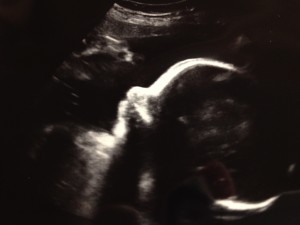

Baby Update- Well Mr. Man, we went to the Dr yesterday, and you are measuring 3lbs 10 oz. That puts you in the 43% percentile and the Dr said that was great and you are one day ahead of your due date. My placenta has moved up out of the way, so I don’t have to have a mandatory c-section. Yay! You were in the head down position and your feet were up by your head, so you were completely folded in half with your butt in my ribs! We got to see you wave your little finger around at us, and it was so cute! They also did a 3D pic of your face, and you definitely have fatter cheeks than the last time we got to see you! Since we are so close to the end (under 9 weeks!) I now start going to our appointments every 2 weeks so the Drs can keep an eye on everything. You’ve been having hiccups that make you really mad so you start squirming around all over the place. According to the baby books, you are about 16 inches long (they don’t actually measure you at the Dr’s office anymore because you are so big and squished up) and about the size of a pineapple. All 5 of your senses are in working order, although your nose won’t pick up anything until after you’re born since smell is transferred through air.

Here are the 3 ultrasound photos from the appointment including one of your boy parts! (Sorry, I know this will be soooo embarrassing when you’re older!)